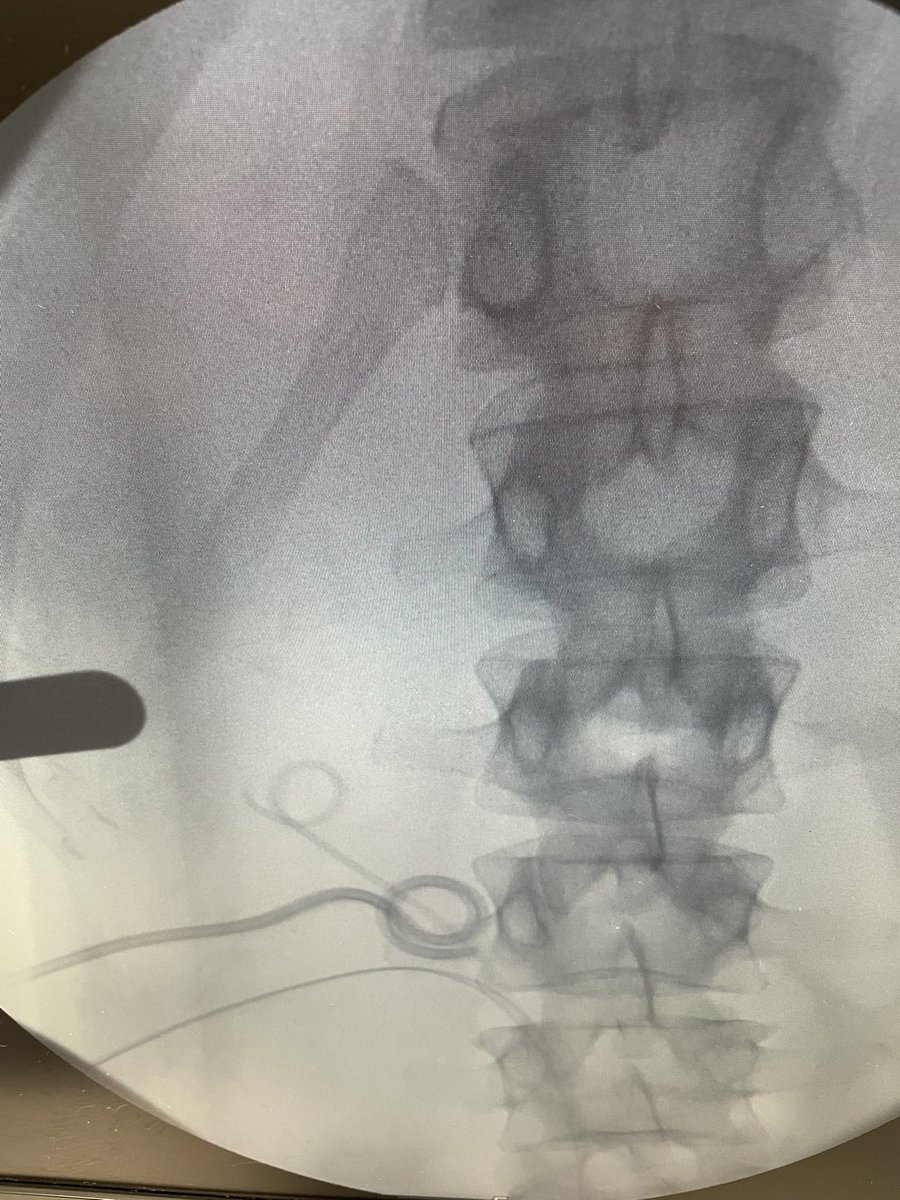

ECIRS miniperc multitract for the traetment of Bety complexión staghorn 2 sessions to complete gaspar ibarluzea Jorge Mora Christian @cruhidisa ECIRS multitrayecto mini para el Tto de la litiasis coraliforme compleja, han sido necesarias 2 sesiones y todo el arsenal Urologia Clinica Bilbao

ECIRS miniperc multitract for the traetment of Bety complexión staghorn 2 sessions to complete <a href="/GasparIbarluzea/">gaspar ibarluzea</a> <a href="/JorgeMoraChris1/">Jorge Mora Christian</a> @cruhidisa

ECIRS multitrayecto mini para el Tto de la litiasis coraliforme compleja, han sido necesarias 2 sesiones y todo el arsenal <a href="/UrologiaB/">Urologia Clinica Bilbao</a>